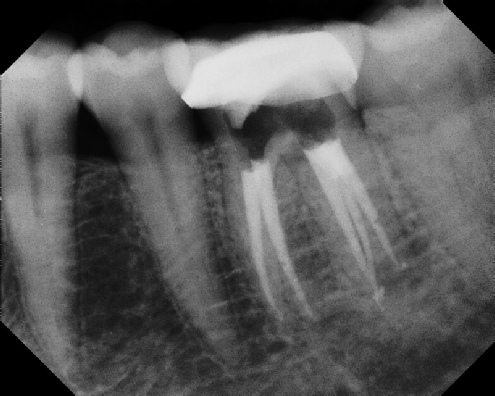

Root Canal Retreatment - Meriden 8 mos. recall Post-op Pre-op